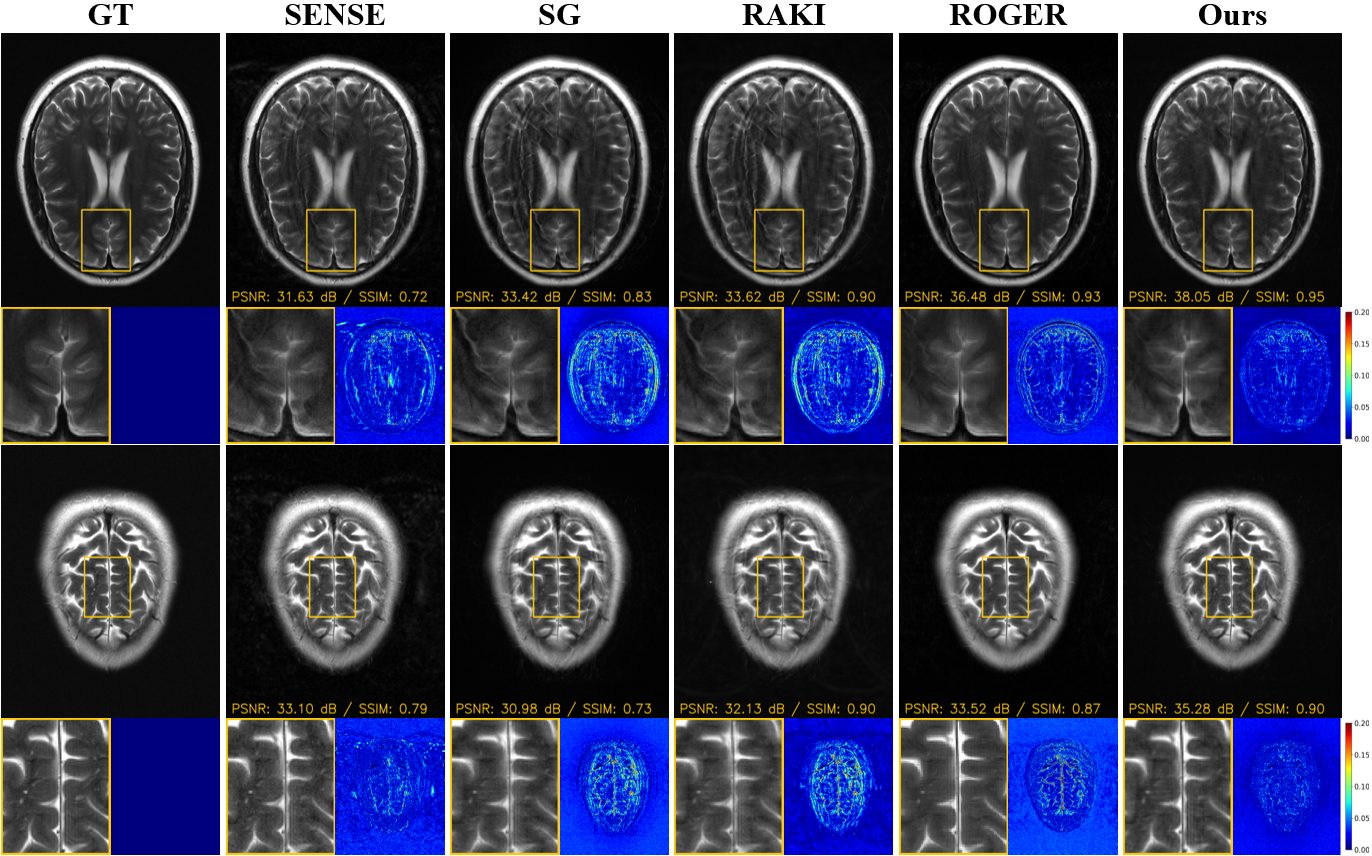

4.2.1 Visual Comparisons on fastMRI

Fig. 4 shows representative visual comparisons under the MB3R2 setting. SENSE exhibits pronounced noise amplification and residual structured artifacts, which blur cortical boundaries and suppress fine anatomical details. Slice-GRAPPA alleviates part of the aliasing but still shows residual slice leakage and loss of high-frequency information. RAKI improves visual sharpness compared with linear baselines but introduces non-uniform residual artifacts in challenging regions. ROGER produces visually smoother reconstructions; however, structured errors remain around complex anatomical boundaries.This behavior is consistent with its Gaussian-noise diffusion formulation, which tends to trade local texture for smoothness when the dominant corruption is operator-governed and structured rather than random. In contrast, OCDI produces reconstructions that are visually closest to the ground truth, with substantially reduced structured errors. This improvement suggests more effective suppression of coherent inter-slice interference while preserving high-frequency slice-consistent details.